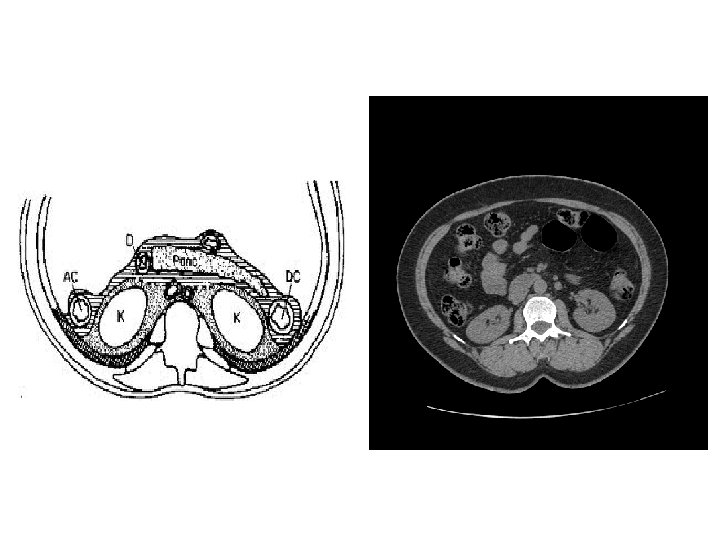

CT • Same basic principle of radiography. • More precise. • Costly. • +/- contrast. • Useful for trauma, stone, tumor, infection.

CT Image features: • Cross sectional images. • Image contrast determined by tissue density +/- contrast. • Better evaluation of soft tissue.